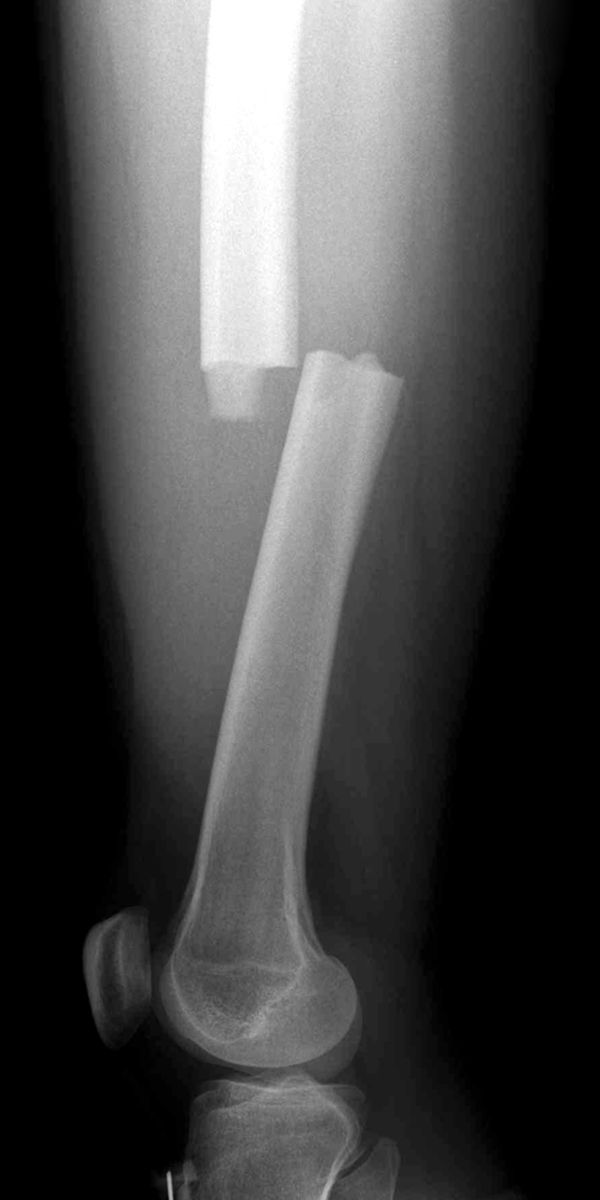

View Femur Bone Fracture Treatment Pics

View Femur Bone Fracture Treatment Pics. During an open reduction, orthopedic surgeons this significantly increases the chance that your bone will heal properly. These patients especially the elderly should be rapidly mobilized to avoid the complication of elderly patients with poor bone stock may be considered for hip replacement surgery in cases of fracture femoral neck and intertrochanteric fractures.

Most femoral shaft fractures require surgery to heal. The strength and size of the treatment of a broken femur involves restoration of the normal anatomical position of the bone fragments, referred to as reduction of the fracture. Growth plates are susceptible to developing fractures in immature animals.

Femur fractures in dogs are the most common fracture and usually the result of major trauma, but they can be caused by disease of the bone itself. The femur, your thigh bone, is the largest and strongest bone in your body. Treating a hip fracture depends on where your hip is broken, how severe the break is is effective pain treatment for spinal fractures caused by osteoporosis or bone tumors. communication: Your thigh bone, or femur, is the largest bone in the human body and as such is also one of the strongest bones in your body.